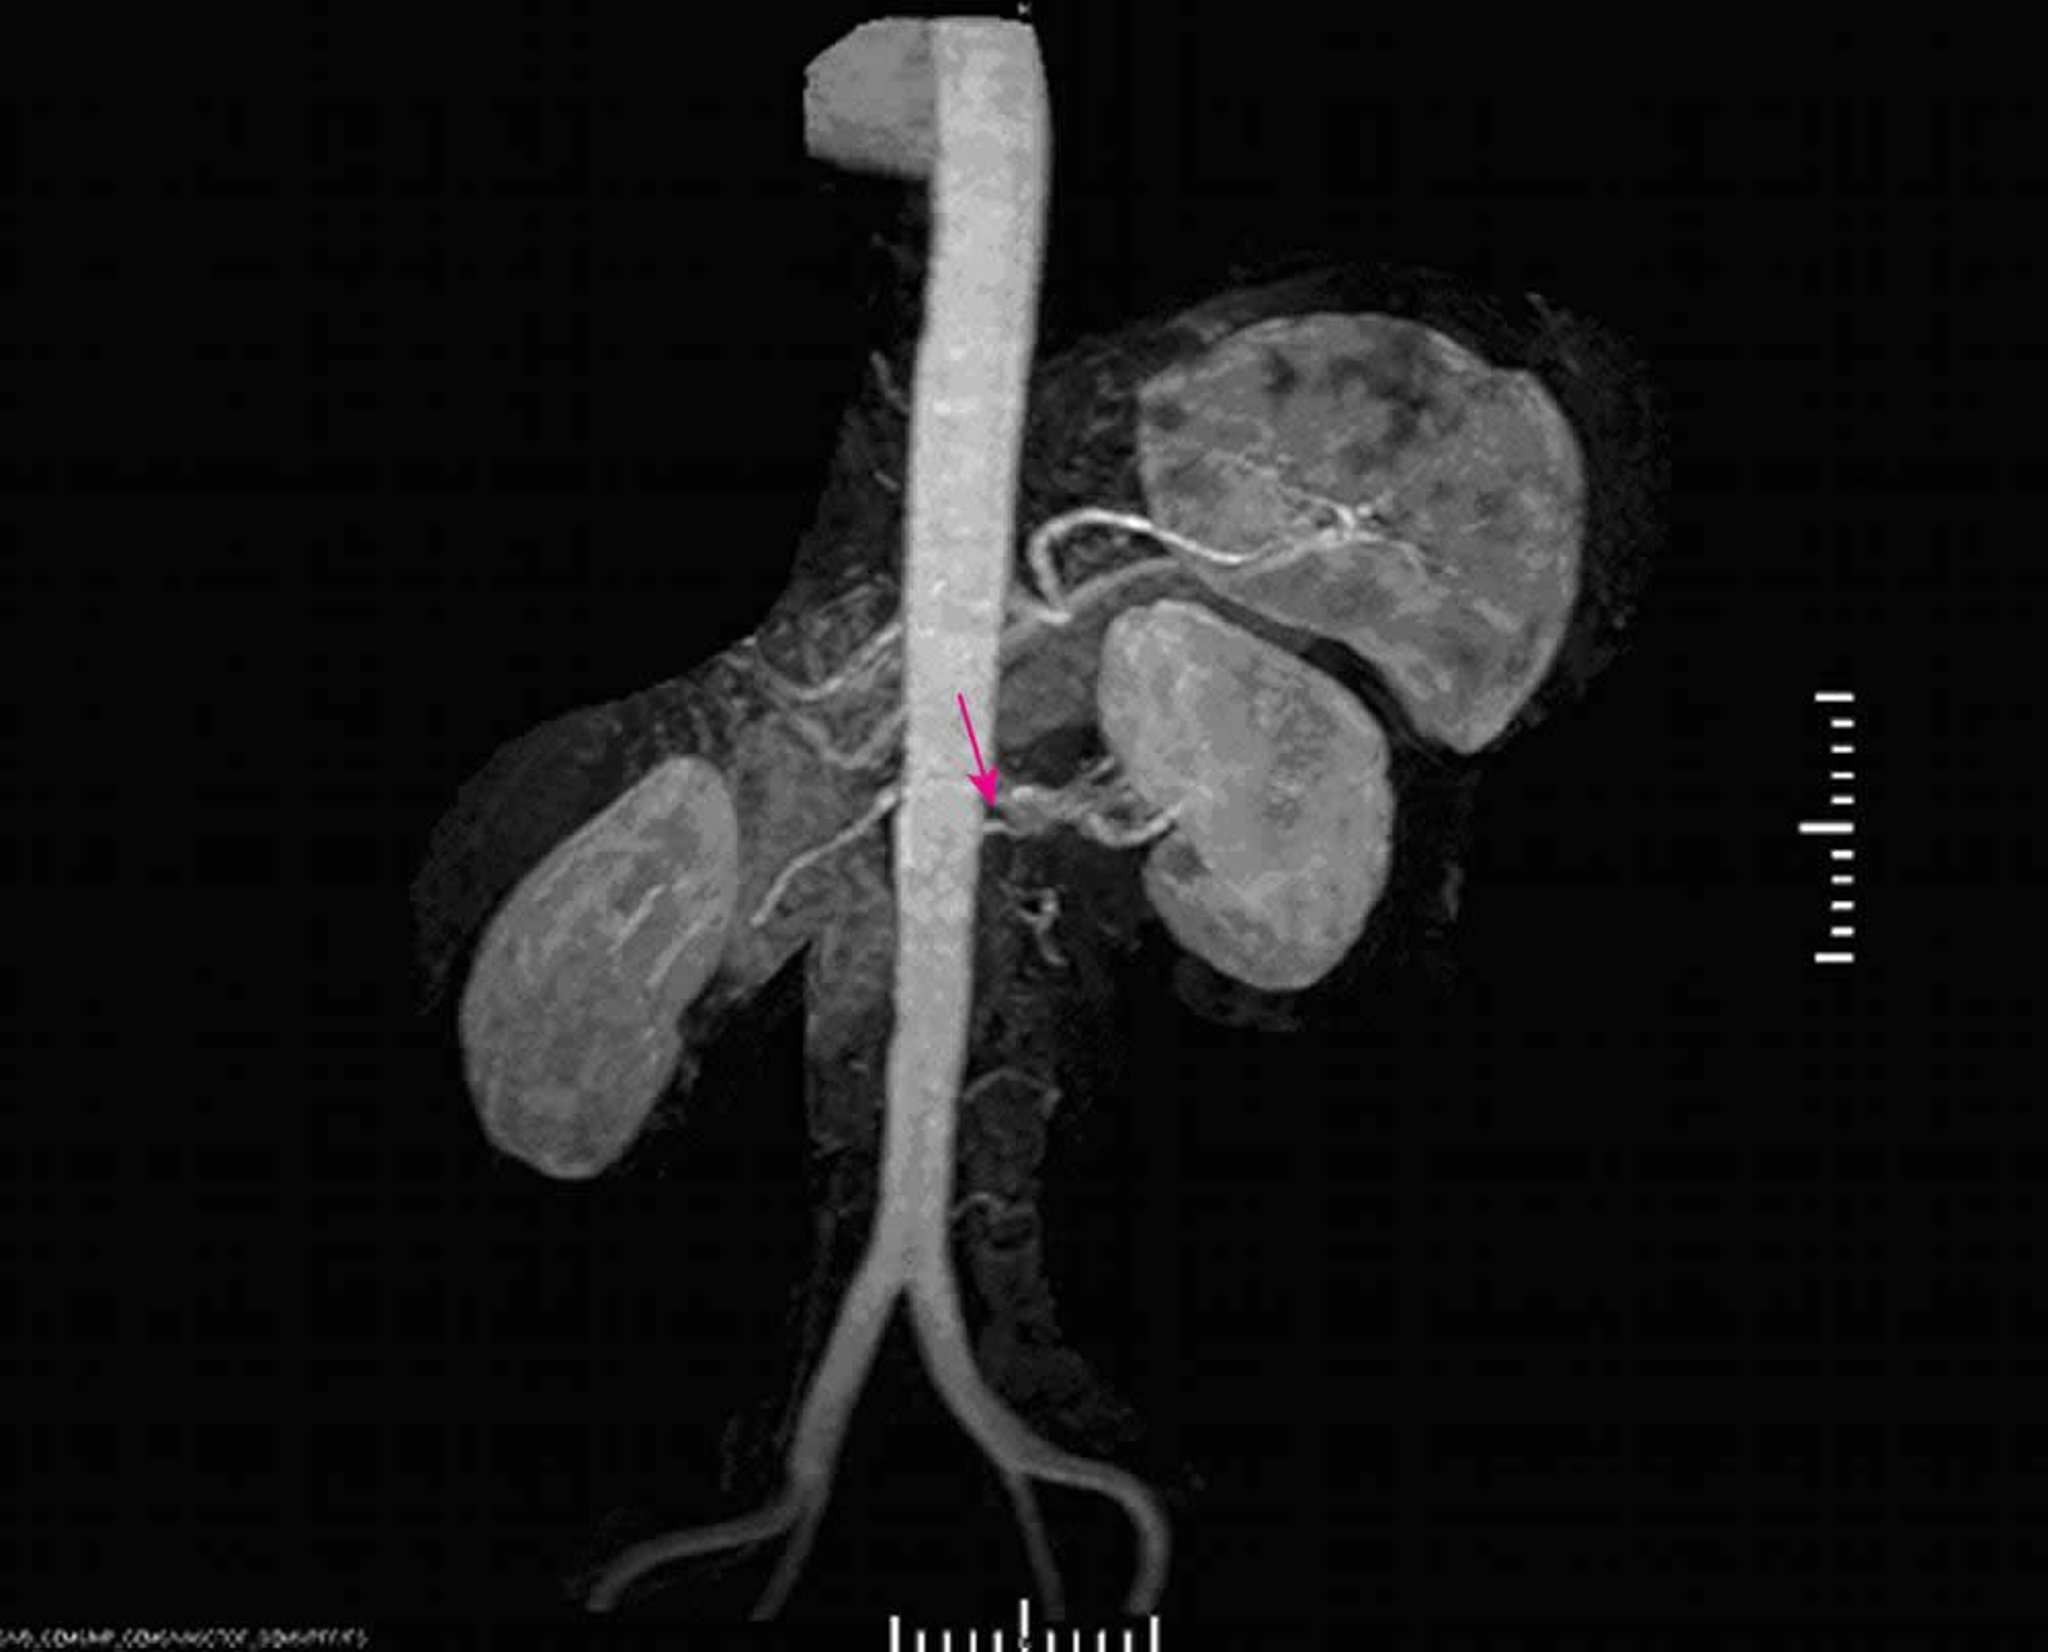

Hipertensão renovascular (angiografia por ressonância magnética)

A angiografia por ressonância magnética revela estenose grave na origem da artéria renal principal esquerda.

Image provided by Jan N. Basile, MD.